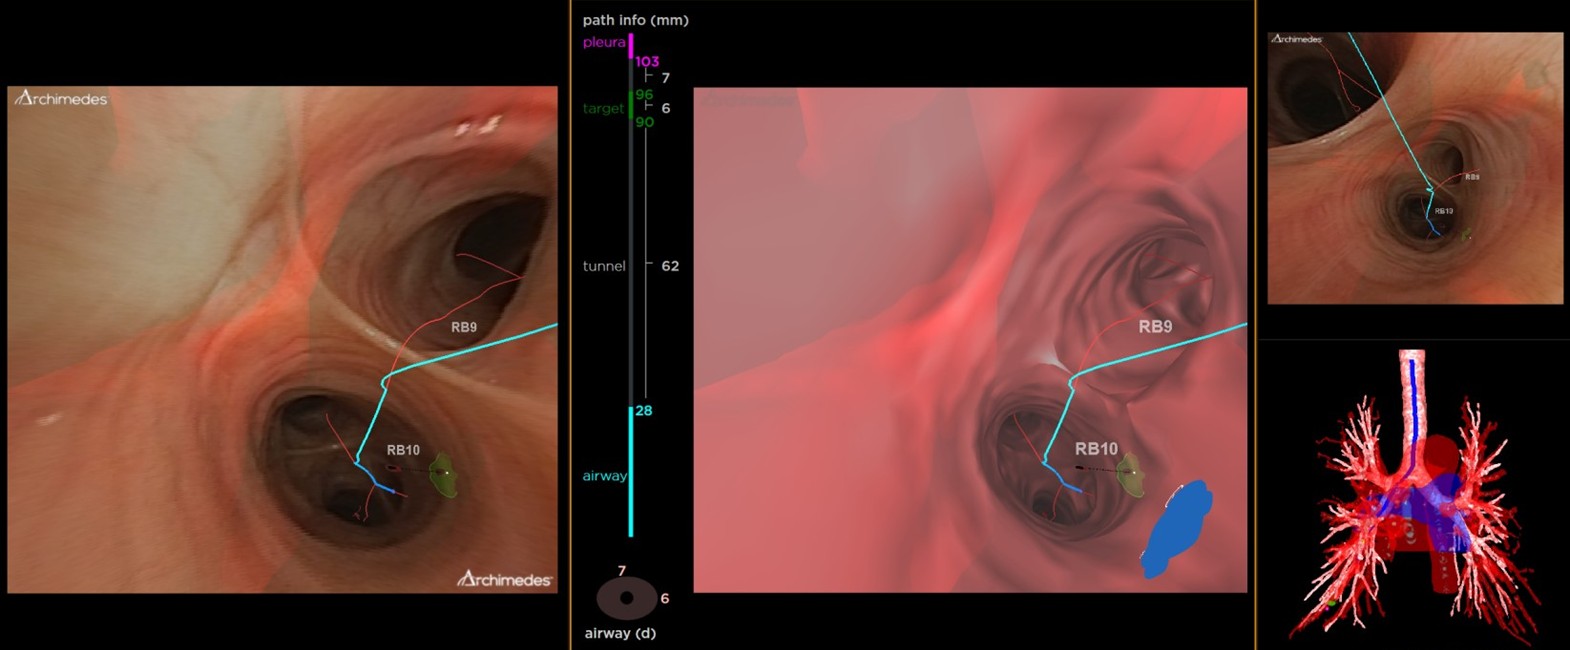

▲阿基米德導航系統以擴增實境技術提供氣管鏡內即時同步影像協助臨床人員精確定位病灶